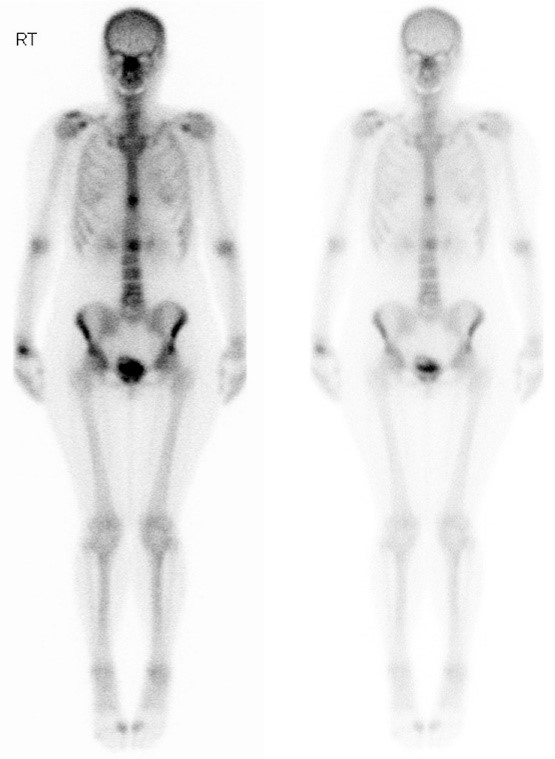

Vous avez fait réaliser une scintigraphie osseuse qui montre l’aspect suivant. Le scanner TAP confirme les localisations osseuses exclusives, hormis un nodule pulmonaire lobaire supérieur droit.

Question 12 - Concernant l’examen ci-dessus et la prise en charge que vous proposez (une ou plusieurs réponses exactes) :

Il existe en effet un hypermétabolisme bilatéral en regard des ailes iliaques.

Il s’agit de la vessie, et du produit de contraste accumulé à l’intérieur.

Une scintigraphie osseuse nécessite l’injection de technétium 99, à la différence d’un TEP-TDM qui nécessite l’injection de 18-FDG.

La scintigraphie osseuse est un examen simple et parfois plus accessible qu’un TEP-TDM.

Elle repose sur l’injection de bisphosphonates marqués au technétium 99, qui se fixe donc dans les zones où l’activité ostéoclastique est importante, dont les métastases osseuses.